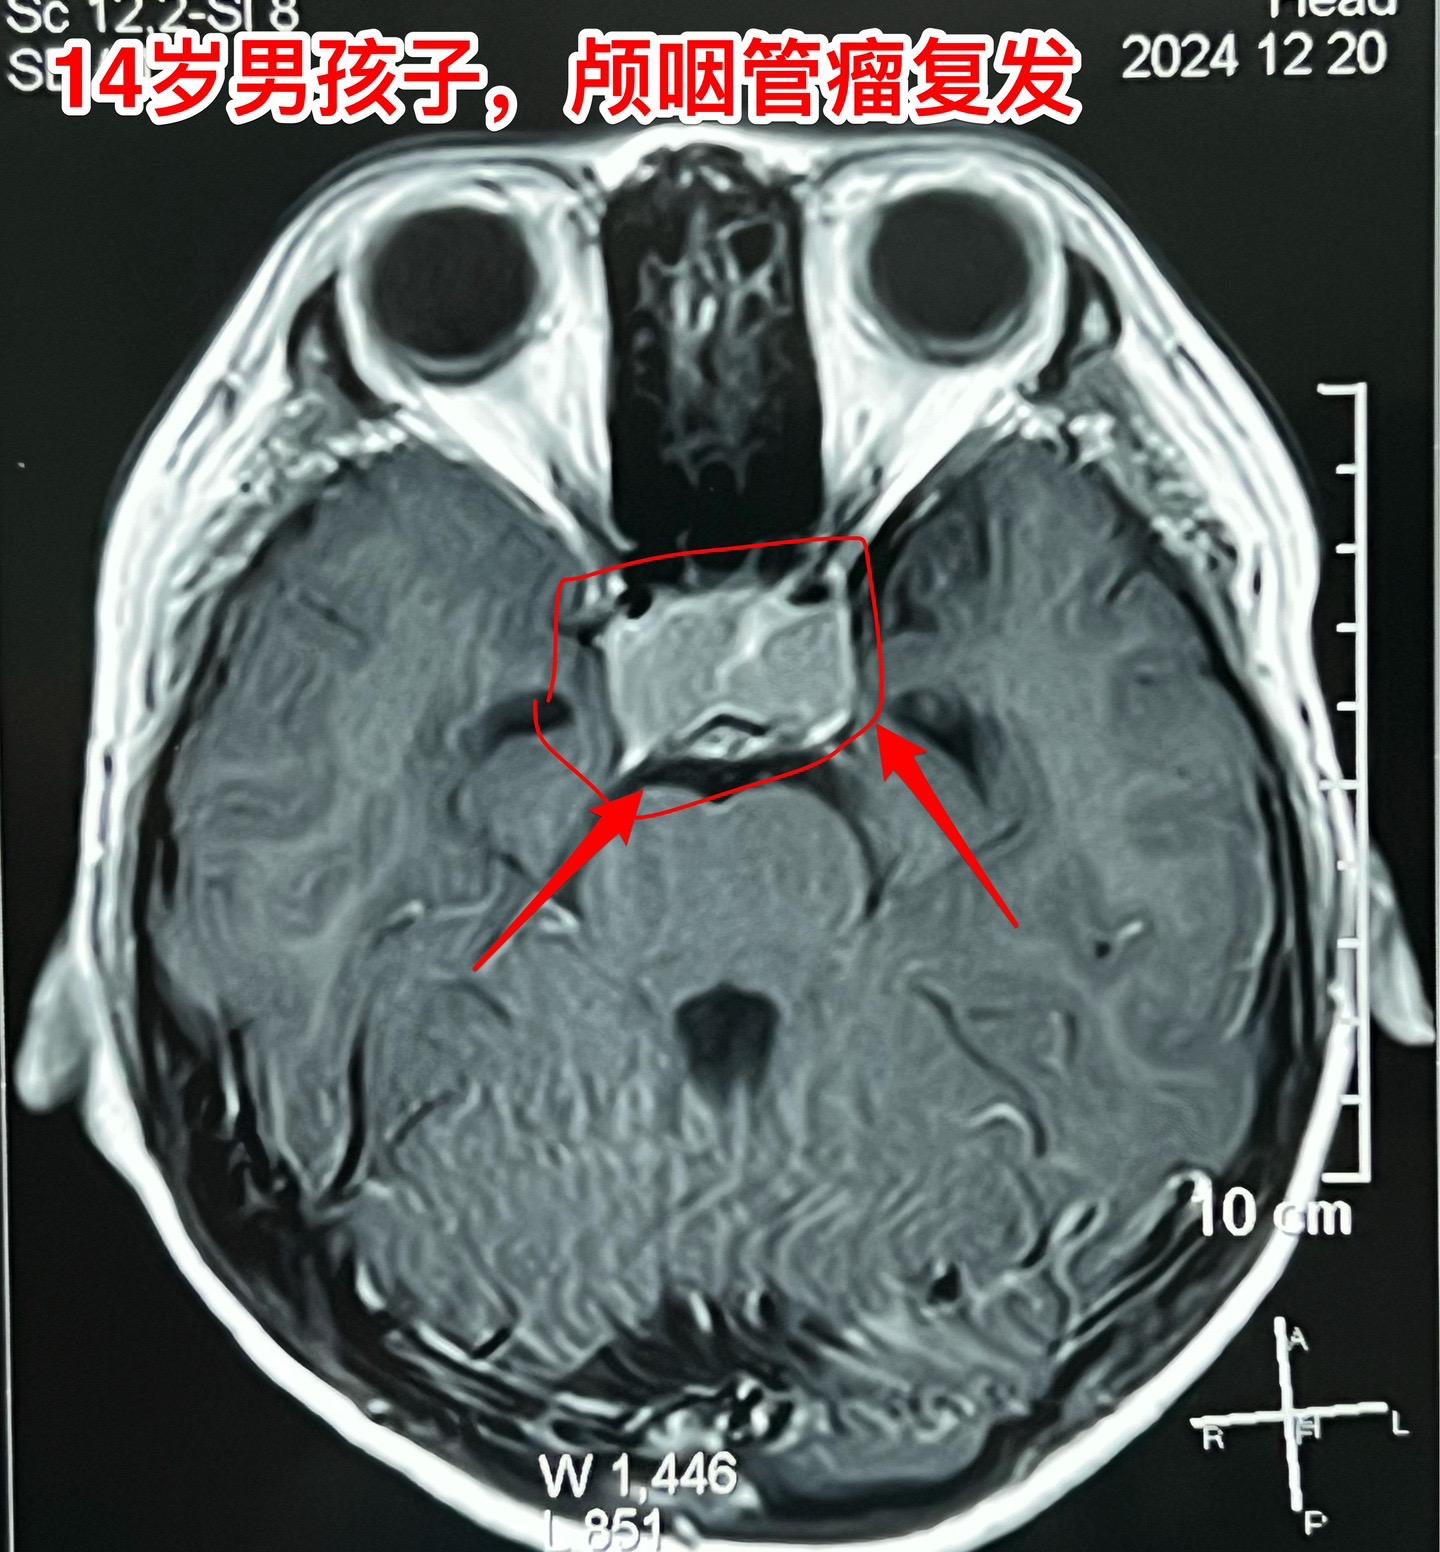

12月26日两个颅咽管瘤手术。第一个四岁男孩子,因为头部受伤,作CT发现颅咽管瘤。家长没有犹豫,选择尽快作手术。手术中将颅咽管瘤完全切除,垂体柄和垂体保留约50%。早作手术的好处就是肿瘤与周围结构粘连不紧密,易于分离,有助于完全切除肿瘤。 第二个病人是14岁男孩子,颅咽管瘤手术后6年,术后半年就发现了肿瘤复发,随后观察,多次复查磁共振显示肿瘤在长大。这个瘤也是在垂体窝内,和第一个病人一样,但是肿瘤与周围结构粘连紧密,切除的难度更大,也得到了完全切除。